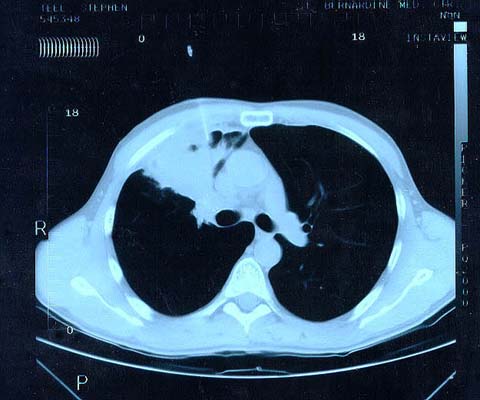

Scan 25th March 1999 No3